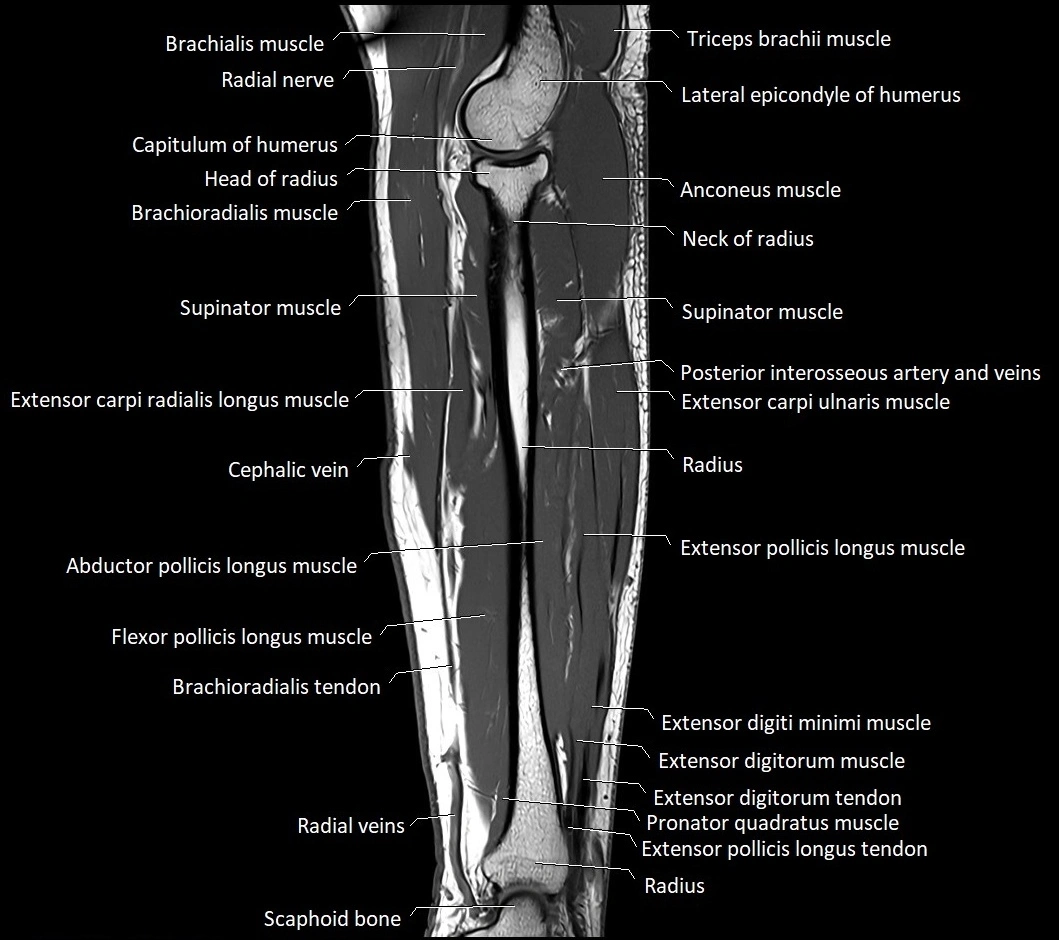

MRI images

image